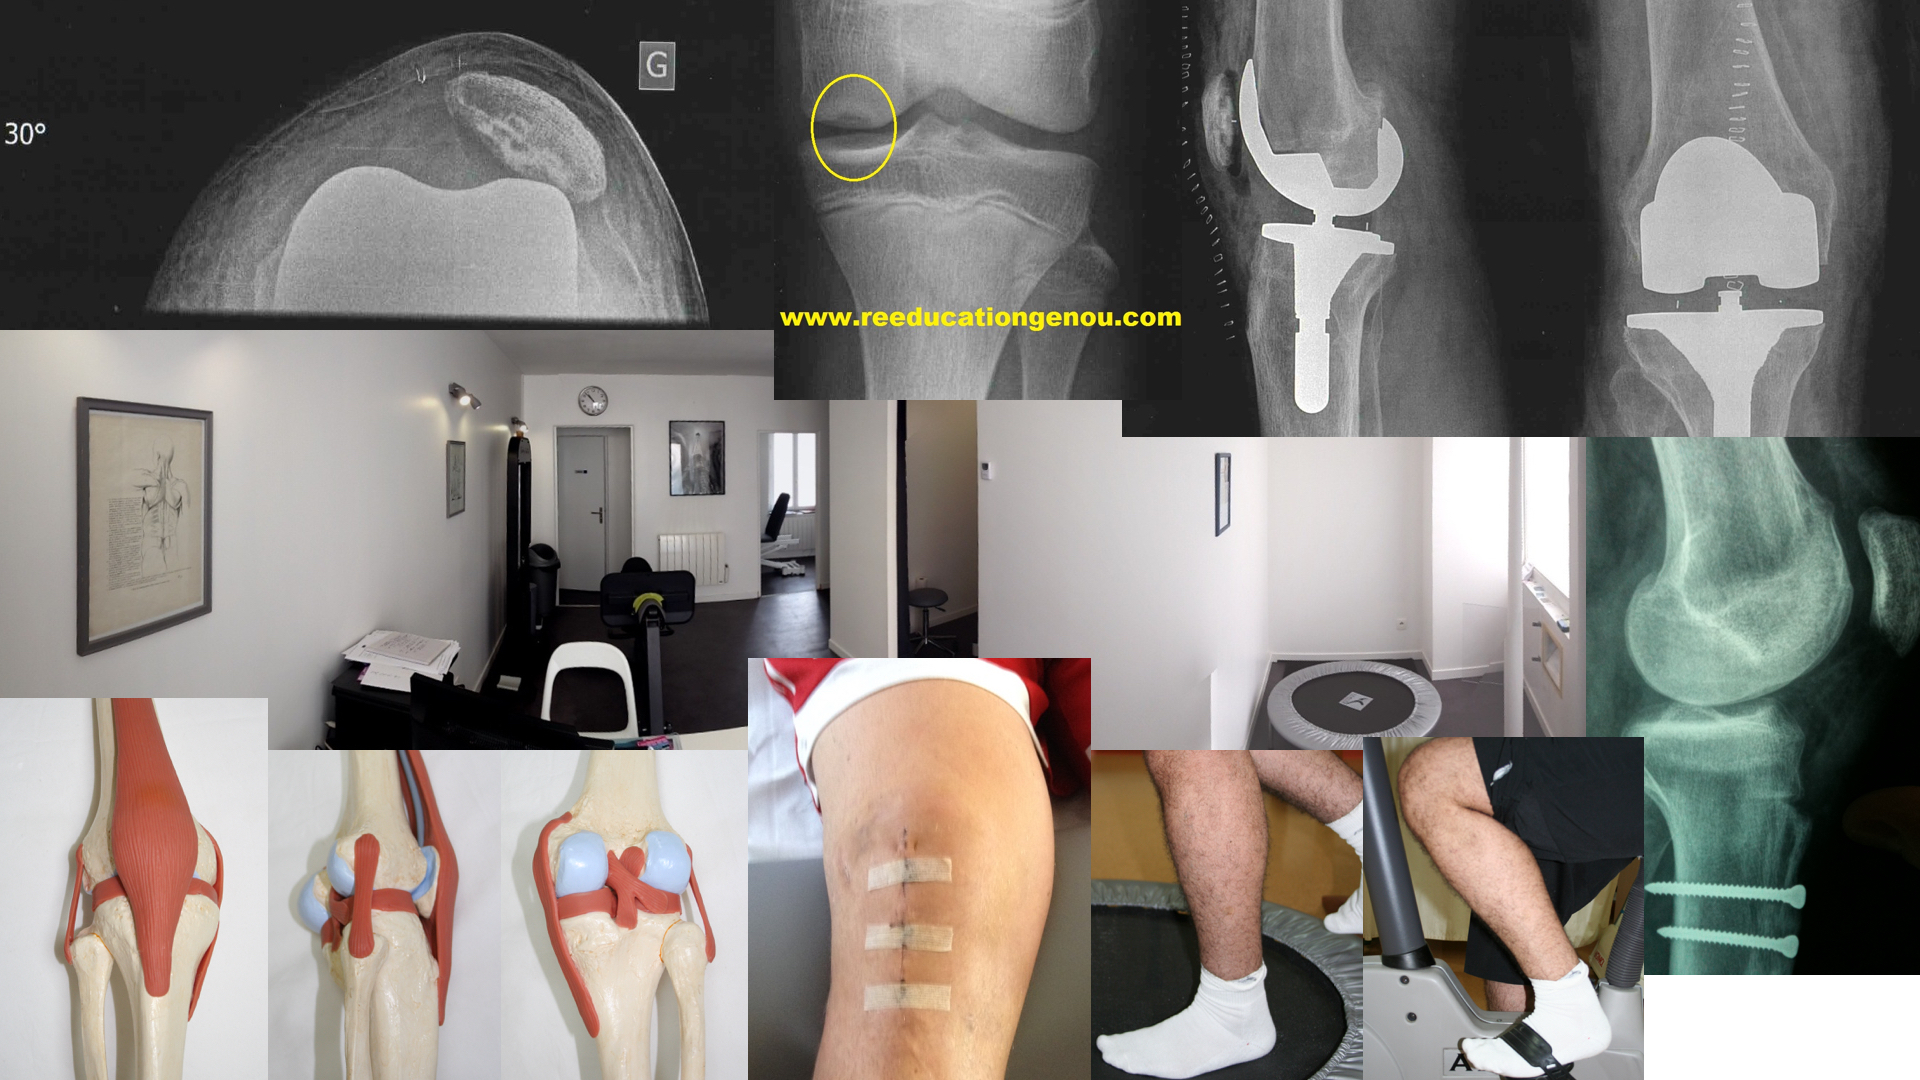

Les étirements musculo-tendineux sont un des grands principes de rééducation après une chirurgie ou non car ils participent à retrouver les amplitudes manquantes, comme à symétriser la force des groupes musculaires entre eux.

Les étirements des muscles pendant la rééducation post opératoire du genou sont essentiels.

En effet le genou est cerné entre plusieurs groupes de muscles puissants comme le mollet, le quadriceps, les ischios jambiers et les muscles fessiers à distance mais importants pour le pas, la marche le saut (et la réception) et la course (sans parler du syndrome rotulien dont une piste de traitement est basée sur la musculationdes fessiers abducteurs)